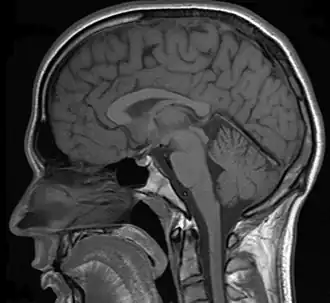

Neuroimaging can be a valuable tool in the diagnostic work-up of various psychiatric disorders including depression.[1]

In a case of misdiagnosed depression recounted in Newsweek, a writer received treatment for depression for years; during the last 10 years of her depression the symptoms worsened, resulting in multiple suicide attempts and psychiatric hospitalizations. When an MRI finally was performed, it showed the presence of a tumor. However, she was told by a neurologist that it was benign. After a worsening of symptoms, and upon the second opinion of another neurologist, the tumor was removed. After the surgery, she no longer had depressive symptoms.[28]